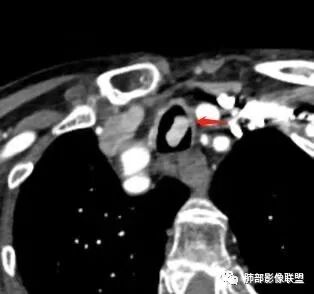

老年女性,两肺多发球形结节,边缘光滑,部分位于胸膜下,纵隔淋巴结肿大不明显,胸水少量,增强后强化明显,考虑转移,肉瘤转移的可能,补充下病史。气管内新生物,是不是二元,息肉或肿瘤

老年女性,间断咯血两年。影像:气管内带蒂结节,边缘光滑明显强化。左肺下叶背段支气管截断,远端不张。两肺散在大小不等结节及磨玻璃影,明显强化,磨玻璃影考虑合并出血可能。纵隔多发淋巴结肿大,两侧支气管受压。综合考虑:肺癌伴两肺转移。原发气管结节还是左肺下叶背段?腺样囊性癌?类癌?

气管占位与肺内肿块血供异常丰富,接近大动脉强化,可以考虑同源

老年女性,病史2年,以咯血丶贫血为主,CT:气管内带蒂肿物丶双肺多发球型团块与结节,明显强化丶程度一致,故考虑同源,富血供。纵隔7组淋巴结肿大,脂肪间隙不清。

右房金属物,可能房颤起搏器